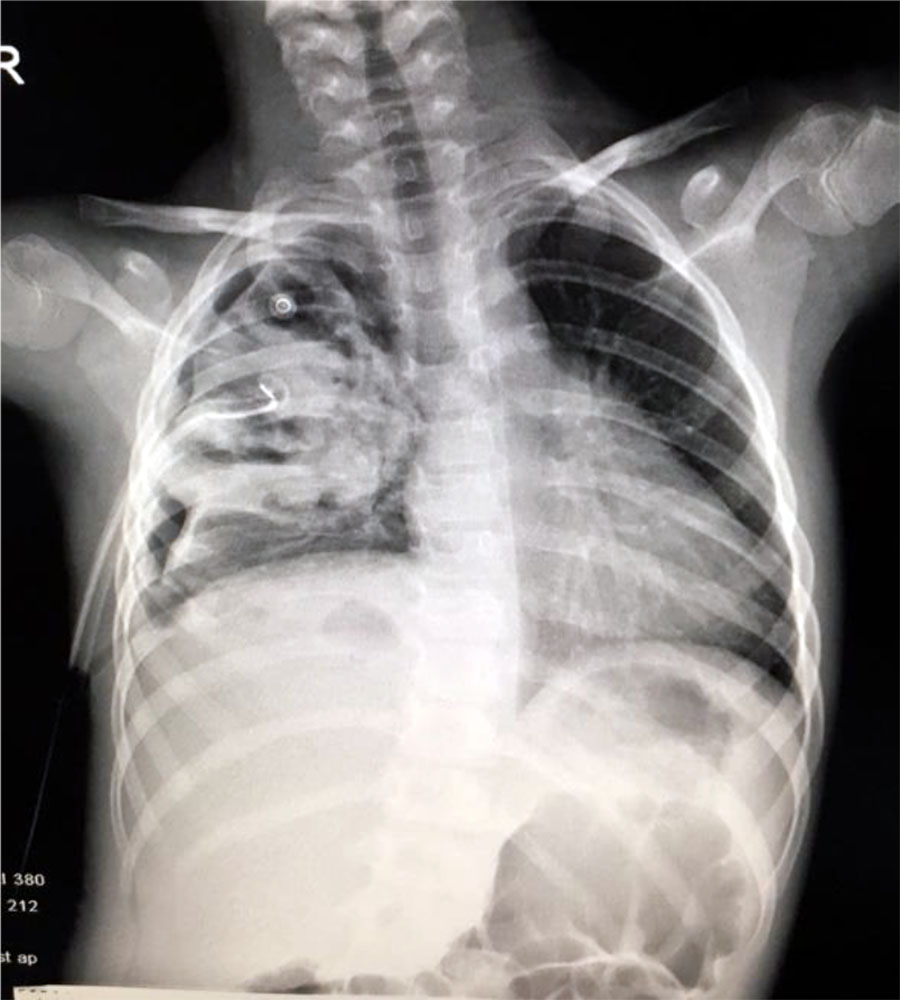

Seven days after the pleural drainage, another chest x-ray was performed. It revealed the maintaining of a non-homogeneous opacity in medium 2/3 of the right hemithorax (Fig. 8). Thus, a video-assisted thoracoscopy (VAT) pleuropulmonary decortication was done (Fig. 9). A subsequent chest x-ray revealed an ameliorated image (Fig. 10). Post-operatory evolution was slowly favorable despite the association between large spectrum antibiotic therapy and systemic antifungal therapy. The patient also needed supportive with rehydration perfusion, immunotherapy and blood transfusion for about one month.

Fig. 8. Non-homogeneous opacity in medium 2/3 of the right hemithorax